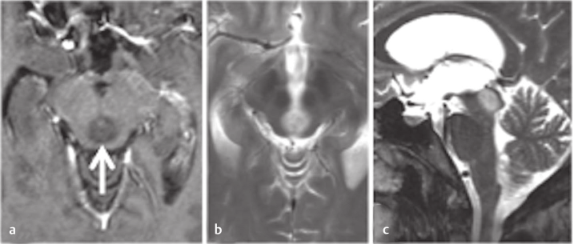

2. 两路包抄全切肿瘤,她也术后11年无复发

36岁的Belle怎么也没想到,持续不断的剧烈头痛和突然出现的走路摇晃,竟是中脑顶盖外生肿瘤在作祟。这个“不速之客”已经引发了阻塞性脑积水,随时可能危及生命。在紧急进行脑室腹腔分流术后,她的症状终于得到缓解。但这个位于脑干的肿瘤,却让医生犯了难。

当找到巴教授,困难将迎刃而解。这位国际脑干大咖精心设计了两路包抄的手术方案:上方经小脑幕上入路精准切入,下方从第四脑室端部巧妙突袭,如同展开一场精妙的“围剿战”。术后影像显示肿瘤被全切,更令人欣喜的是,Belle的神经功能完全未受影响。组织病理学诊断为形成菊形团的胶质神经元肿瘤(RGNT)。

术后11年随访,肿瘤无复发。术后享受着正常人的生活。